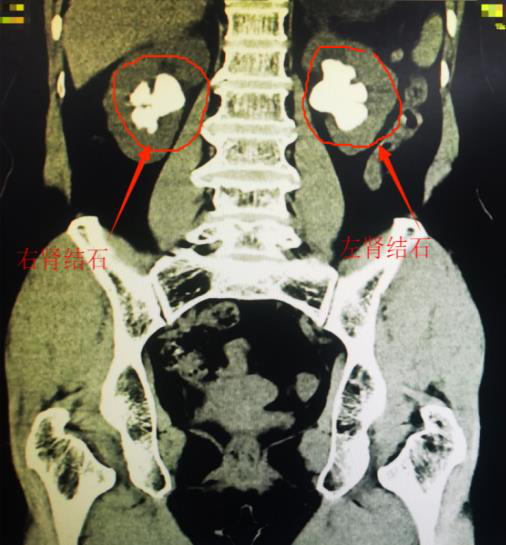

患者陈阿姨今年61岁,发现肾结石已有5年多,多次服用中药排石治疗,效果不佳,不但没有排出结石,且复查彩超提示肾结石逐渐增多、增大。在饱受腰痛、血尿折磨后,陈阿姨在家人的陪同下来到我院就诊,希望通过微创手术治疗肾结石,解除病痛。陈阿姨入院后医生为其完善了CT检查,只见她的双肾都已被结石填满,是临床上非常棘手的肾铸型结石。

▲CT检查提示陈阿姨双肾被结石占满